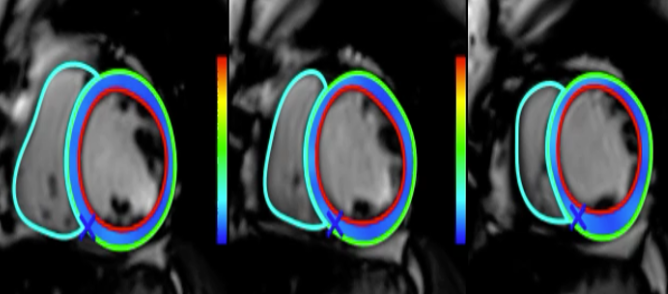

CMR strain assessment